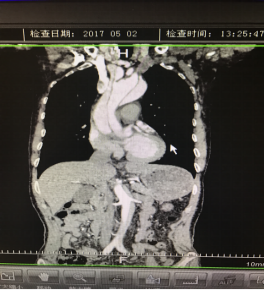

5月2號劉大伯照常早起干活,突然胸部劇烈疼痛,難以忍受,全身大汗,同時伴有右上肢發(fā)涼,他心想這次心絞痛比之前嚴重的多啊,趕緊叫上孩子到吉林國文醫(yī)院心血管內科住院,患者長期高血壓病史,血壓一直控制不理想,大夫給他做了檢查,測左上肢血壓:82/45mmHg,右上肢血壓測不出,心率52次/分,右側肱動脈、尺動脈、橈動脈搏動消失,左側股動脈搏動較右側弱?!霸懔耍p側血壓差別這么大,是不是主動脈夾層了?”,接診大夫趕緊找來李主任,李主任反復詢問患者病情,表情突然凝重起來,患者胸痛這么明顯,血壓低的厲害,主動脈夾層的可能性很大。二話不說,李主任立即聯(lián)系影像科的醫(yī)生準備做主動脈CTA,移動患者做檢查的過程大夫們非常小心,嚴密監(jiān)測患者血壓變化情況。兩個小時后結果出來了,主動脈夾層從升主動脈一直撕裂到左側髂總動脈!?。?/p>

從開始學醫(yī)到現(xiàn)在已經(jīng)快9年了,主動脈夾層患者也見過一些,但像劉大伯這種危險類型的還是第一次見到,心里真的為他捏把汗,撕裂的主動脈隨時都有可能破裂,生命隨時可能終止,要知道主動脈夾層的死亡率非常的高,約50%的患者發(fā)病后48小時死亡,約90%的患者發(fā)病1個月內死亡。